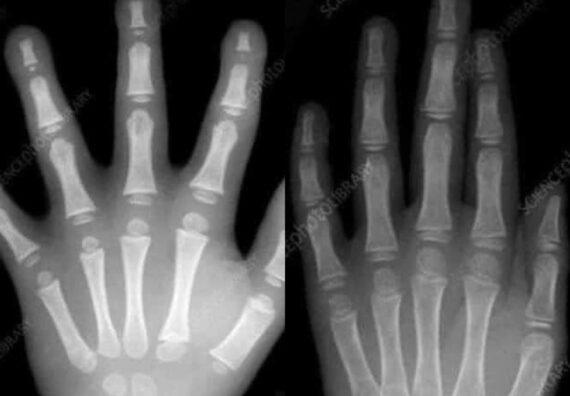

Αριστερά το χέρι ενός παιδιού προσχολικής ηλικίας. Δεξιά το χέρι ενός παιδιού 7 ετών. Κοιτάξτε τις διαφορές. Θέλετε να μάθετε γιατί ένα παιδί προσχολικής ηλικίας δεν μπορεί να γράψει ακόμα; Αυτός είναι ο λόγος! Τα χέρια τους εξακολουθούν να αναπτύσσονται και δεν είναι πλήρως διαμορφωμένα.